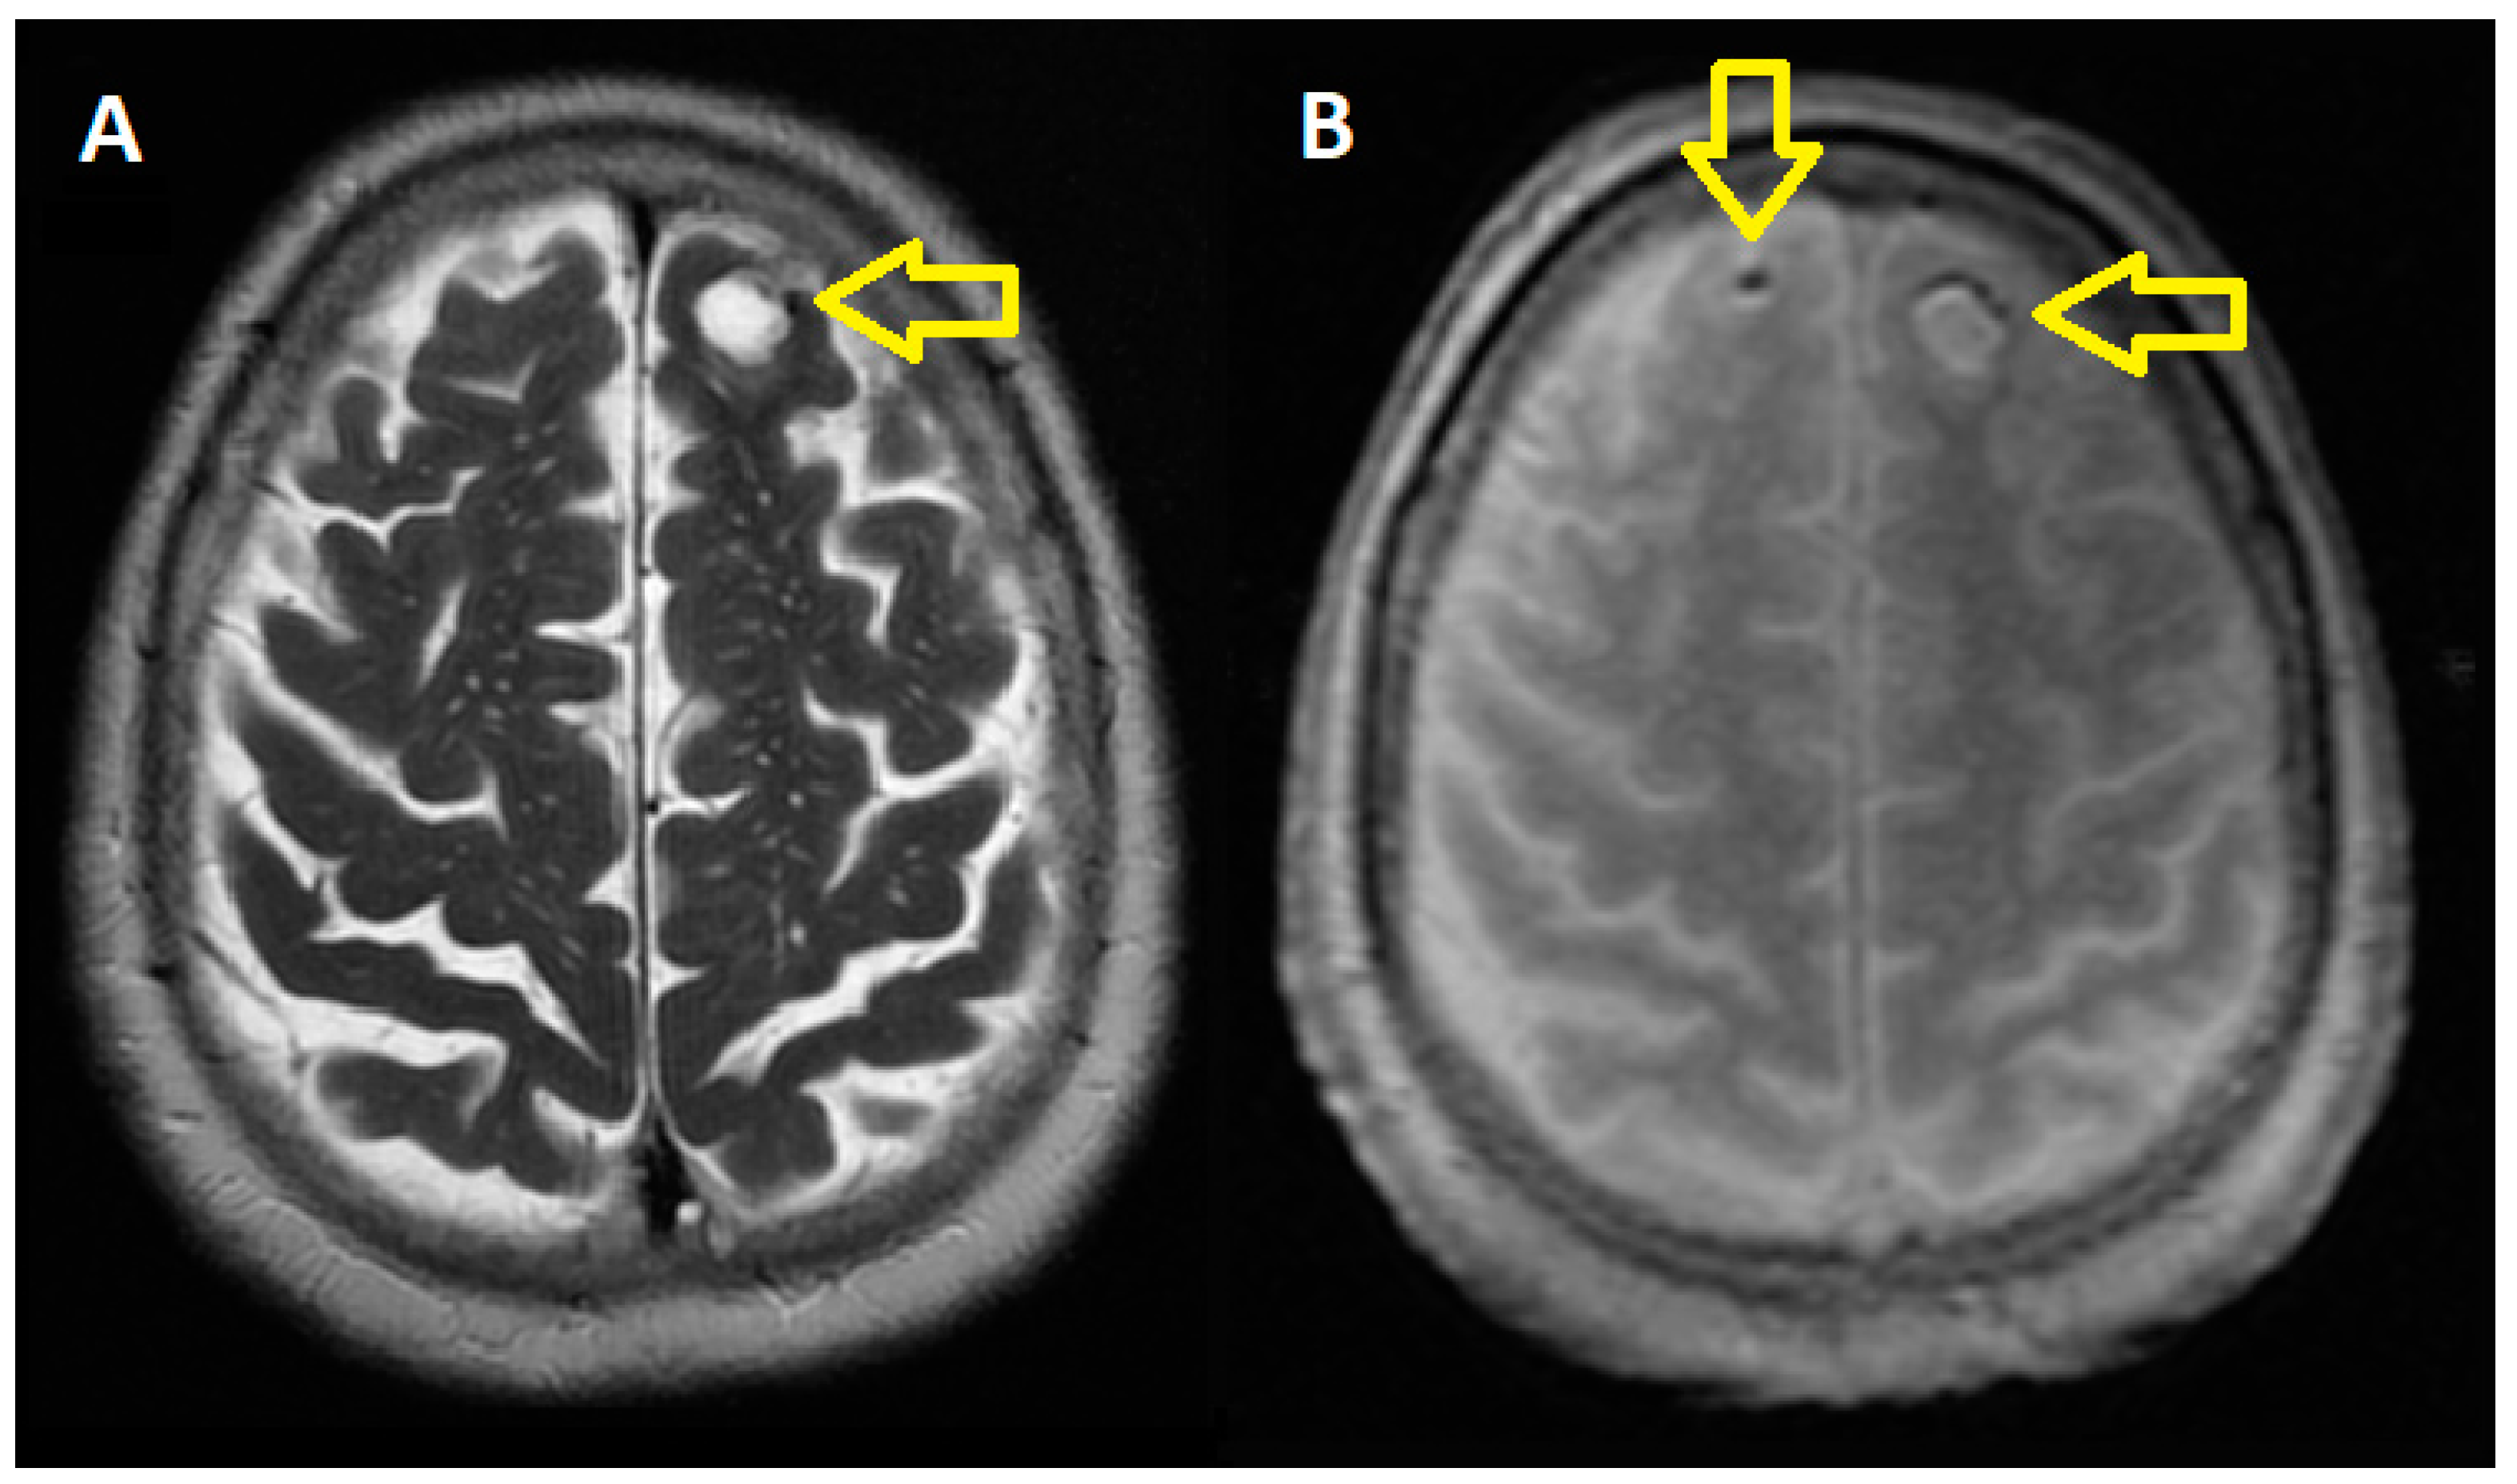

2.1. At the Cerebral Level